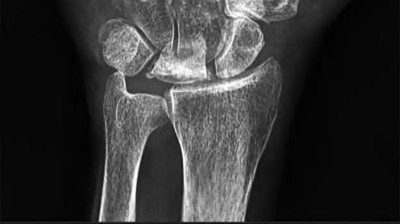

A 35-year-old woman reports wrist pain after a fall onto an outstretched hand. On exam, she has focal tenderness over the wrist snuffbox. A radiograph and CT image are shown in Figures A and B. What is the proper treatment of her injury?